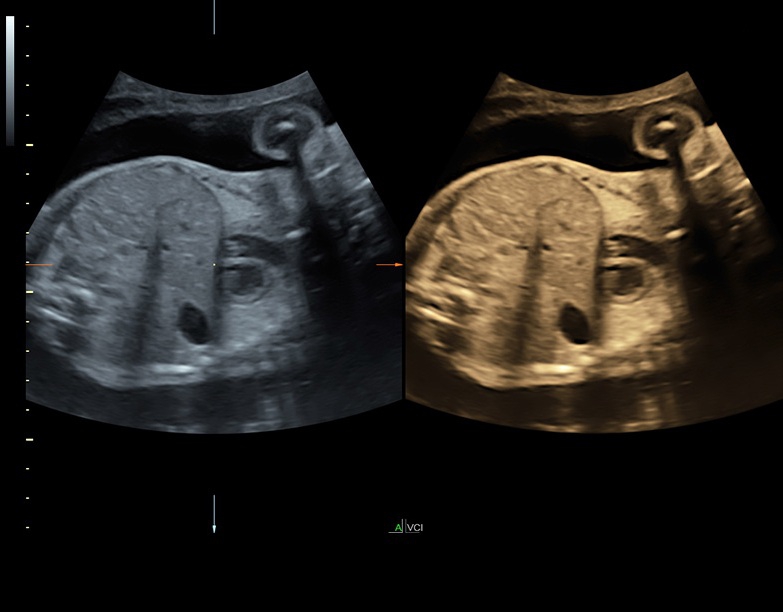

• Расширенный программный пакет объемного контрастного изображения (VCI) для объемных датчиков

• Технология SonoRenderlive: Эта технология облегчает получение 3D/4D изображений путем автоматического изменения положения плоскости визуализации в зависимости от движений плода. Она позволяет получить реалистичные и объемные изображения, что полезно для демонстрации плода будущим родителям и для дополнительного анализа.